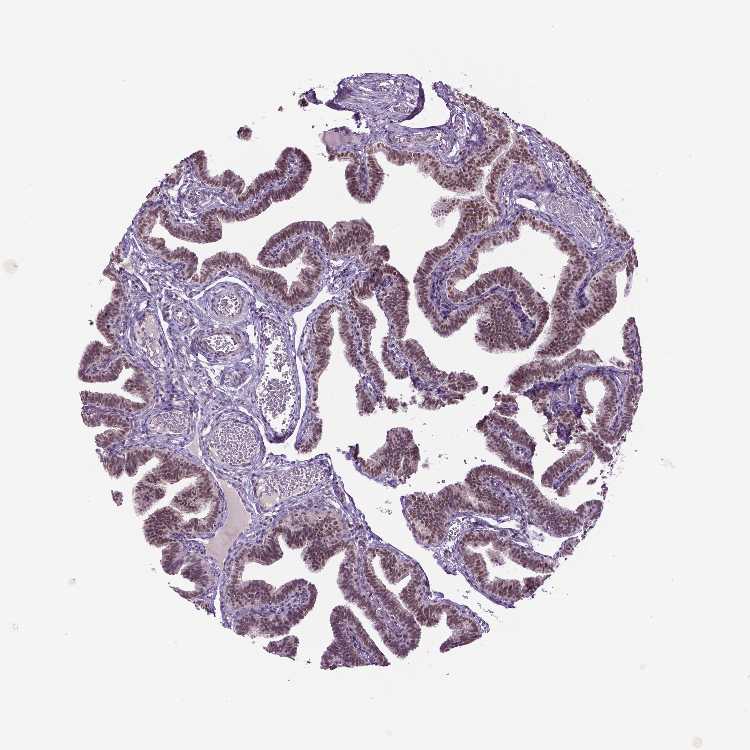

FALLOPIAN TUBE - Antibody stainingi

Antibody staining in the annotated cell types in the current human tissue is reported as not detected, low, medium, or high, based on conventional immunohistochemistry profiling in selected tissues. This score is based on the combination of the staining intensity and fraction of stained cells.

Each image is clickable and will lead to virtual microscopy that enables deeper exploration of all samples and also displays staining intensity scores, fraction scores and subcellular localization as well as patient and tissue information for each sample.

Antibody HPA069538

Ciliated cells (cell body) Medium

Ciliated cells (cilia axoneme) Not detected

Ciliated cells (ciliary rootlets) Low

Ciliated cells (tip of cilia) Low

Non-ciliated cells Medium